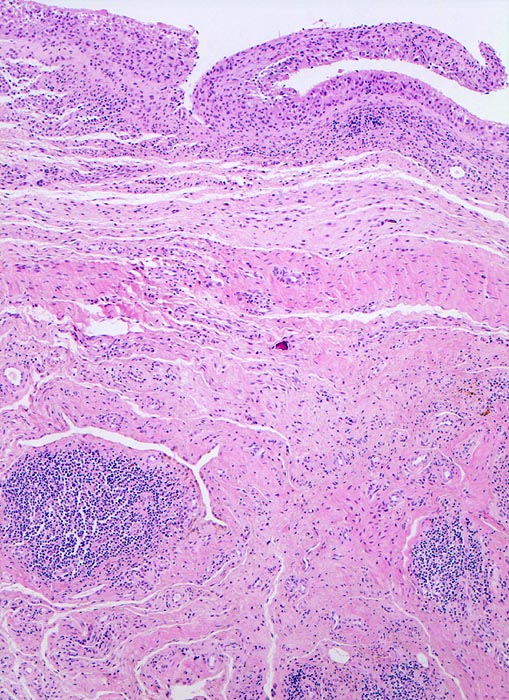

In Abhängigkeit von der Entzündungsdauer werden unterschiedliche morphologische Befunde beschrieben. Die initiale proliferative Phase ist charakterisiert durch eine Hyperplasie der Synovialis, Fibrinexsudate und Gelenkergüsse. In der destruktiven Phase kommt es zur Zerstörung von Gelenkknorpel und gelenknahem Knochen durch Ausbildung eines intraartikulären Pannusgewebes (> 194). Die ausgebrannte Phase ist gekennzeichnet durch eine synoviale Fibrose mit zunehmender Ankylose (= Gelenkversteifung).

Typische histologische Veränderungen sind eine synoviale Zottenhyperplasie, Verbreiterung der Deckzellschicht unter Einschluss mehrkerniger Riesenzellen, Fibrinexsudate und synoviale Ulzerationen, Infiltrate von Lymphozyten teils in Form von Lymphfollikeln, Plasmazellen, neutrophilen Granulozyten, Makrophagen und Siderophagen, sowie Einschlüsse von Knorpel- und Knochenfragmenten (Detritussynovialitis). Die histologischen Befunde der Synovialis korrelieren oft nicht mit den klinischen Angaben. Trotz fortgeschrittener Gelenkdestruktion mit ausgeprägter klinischer Symptomatik können Synovialektomiepräparate nur sehr geringe pathologische Veränderungen zeigen. Oft ist auch nicht mehr zu eruieren, welche Läsionen Folge der Grundkrankheit und welche Folge diverser intraartikulärer Therapien oder begleitender Superinfektionen sind.

• Synovialis mit verplumpten Zotten.

• Stark proliferierte mehrreihige synoviale Deckzellschicht.

• Herdförmig Fibrinauflagerungen durchsetzt von neutrophilen Granulozyten.

• Hyperzelluläres Stroma mit lymphoplasmazellulärem Entzündungsinfiltrat mit Ausbildung von Lymphfollikeln.